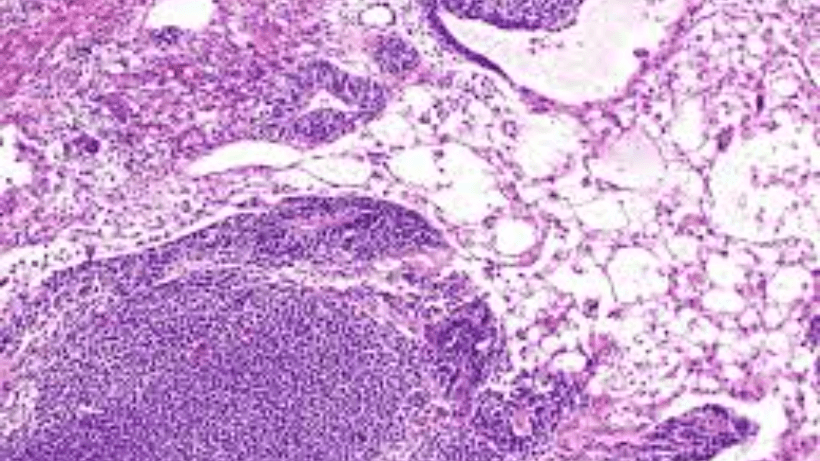

1. Dysgerminoma:

Dysgerminomas በጣም የተለመዱ የእንቁላል እጢዎች አደገኛ የጀርም ሴል እጢዎች ናቸው. ብዙውን ጊዜ በጉርምስና እና ወጣት ሴቶች ላይ ይከሰታሉ. Dysgerminomas ለጨረር እና ለኬሞቴራፒ በጣም ስሜታዊ ናቸው, እና በምርመራ እና በጊዜ ሲታከሙ ጥሩ ትንበያ ይኖራቸዋል..